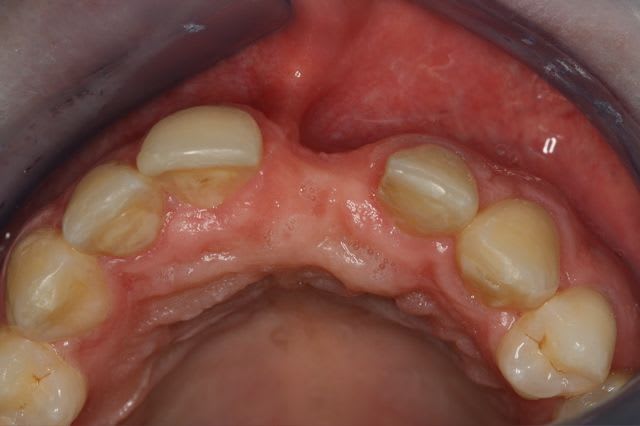

Pour le fun ! car pas bcp de photos en ce moment sur nonol

la dent était absente depuis 8 ans suite à "accident" de la vie (à 5h du mat'...)

dépose des vis et pose de l'implant à 5mois1/2 avec un cj roulé et mise en place de la vis de cica,

et 3 mois 1/2 après empreinte

15j après essayage pilier et biscuit, visite au labo pour "finition en bouche" et 3 h après scellement.

en temporisation, la vieille PAP du patient (raison €€€ )